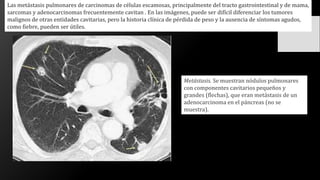

Las metástasis pulmonares de carcinomas de células escamosas, principalmente del tracto gastrointestinal y de mama,

sarcomas y adenocarcinomas frecuentemente cavitan . En las imágenes, puede ser difícil diferenciar los tumores

malignos de otras entidades cavitarias, pero la historia clínica de pérdida de peso y la ausencia de síntomas agudos,

como fiebre, pueden ser útiles.

Metástasis. Se muestran nódulos pulmonares

con componentes cavitarios pequeños y

grandes (flechas), que eran metástasis de un

adenocarcinoma en el páncreas (no se

muestra).